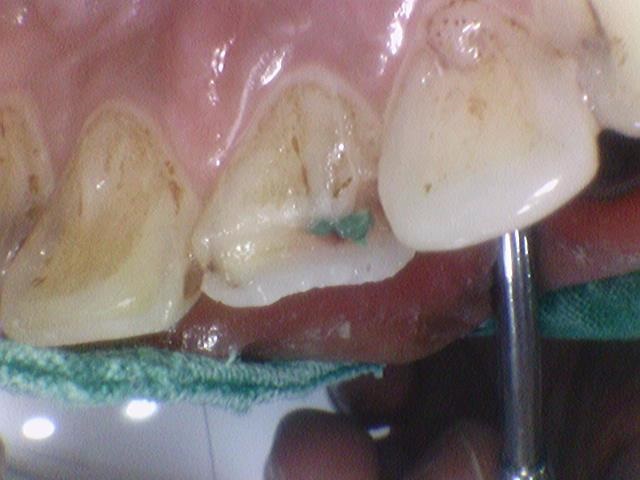

방금 넘어져서 앞니가 깨졌다며

잘하는 치과 수소문해서 소개받고 오신 외국인환자분입니다.

앞니깨짐

처음에는 크라운을 하면 될거라 예상했지만

자세히 보니 앞니가 뿌리 부분까지 쪼개져서 벌어져 있었습니다.